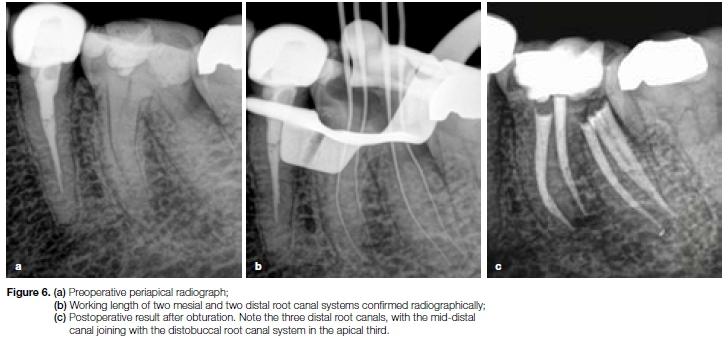

Case report

The patient, a 41 year old female presented with a non-vital mandibular left first molar (Figure 6a). After access cavity preparation, four root canal systems were detected (mesiobuccal, mesiolingual, distobuccal and disto-lingual) and length determinations were confirmed radio-graphically (Figure 6b). Glide path preparation was done with a ProGlider (Dentsply Sirona).

After glide path preparation another distal canal (mid-distal) was detected. Root canal preparation of the Ave root canal systems were done with the S1, S2, F1 and F2 ProTaper Gold instruments.

Figure 6c depicts the final result after root canal obturation with Protaper Gold F2 Gutta Percha Points (Dentsply Sirona) and Pulp Canal Sealer (Kerr, Bioggio, Switzerland), using System B (Kerr) and Obtura II (Obtura Spartan) obturation units. Note that the mid-distal canal joins in the apical third with the distobuccal root canal system to end in one apical foramen.